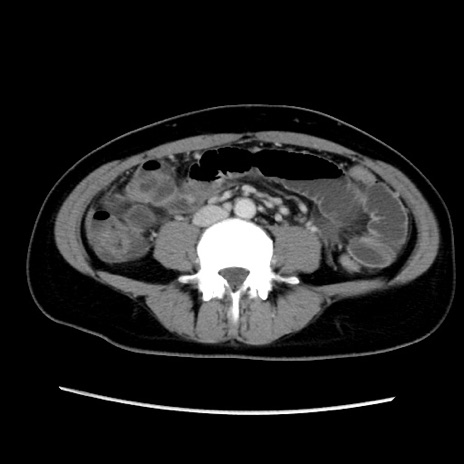

MRI(4日後)

【症例】40歳代女性

【主訴】上下腹部痛

【現病歴】2日目から下腹部痛あり。夜間は痛みで眠れなかった。昨日より上腹部痛と下痢が出現。臥位で痛みは軽快したため、休んでいた。本日になって臥位でも立位でも痛みが強くなってきたため救急要請。

【既往歴】子宮内膜症

【身体所見】部:平坦・軟、左上下腹部に圧痛あり、反跳痛あり。

【データ】WBC 21800、CRP 26.78